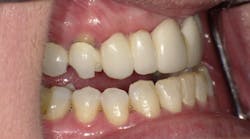

Left side prior to restorative treatment

Right side prior to restorative treatment; note the fractured bridge

Pretreatment anterior view; maxillary bridge Nos. 3–14 with a pontic span Nos. 6–11